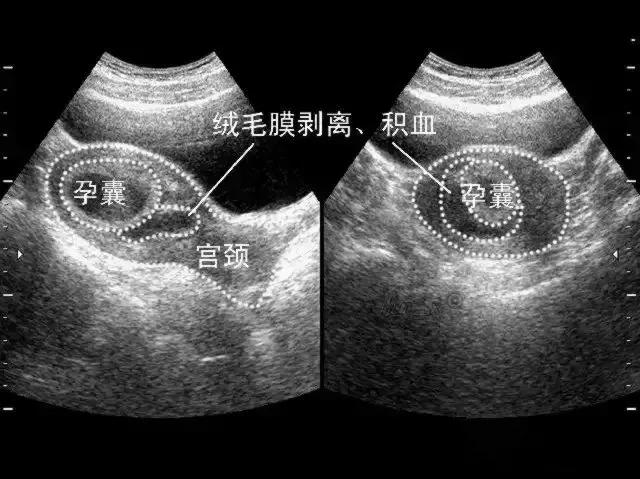

绒毛膜下血肿是指由于绒毛膜与蜕膜之间分离,局部出血积聚而成。不同大小的血肿总是在叶状绒毛膜、平滑绒毛膜与底蛻膜、包蛻膜之间。超声检查可见胎膜与蜕膜部分剥离,其间呈无回声液性暗区,血肿较大有凝血块时其内可见点状、线状或云状高辉度像,轮廓较明显,常位于胎盘下缘,多呈新月状,其血肿下缘常与子宫内口相通,而出现阴道流血。多发生早中孕期。报道的发生率为4%~48%不等。

- 绒毛膜下血肿的超声声像表现为液体集聚在妊娠囊与子宫壁之间,可呈新月形、圆形等多种形状,液体外形取决于子宫的形态变化。血肿局部多普勒检测不到血流信号。

(1)血肿急性期(0~48 h):血肿回声高于妊娠囊壁或叶状绒毛膜。(2)血肿亚急性期(3~7 d):血肿回声近似于妊娠囊壁或叶状绒毛膜,血肿内回声表现趋复杂,如纤维条带样、团块状等。(3)血肿慢性期(>7 d):血肿呈低或无回声。